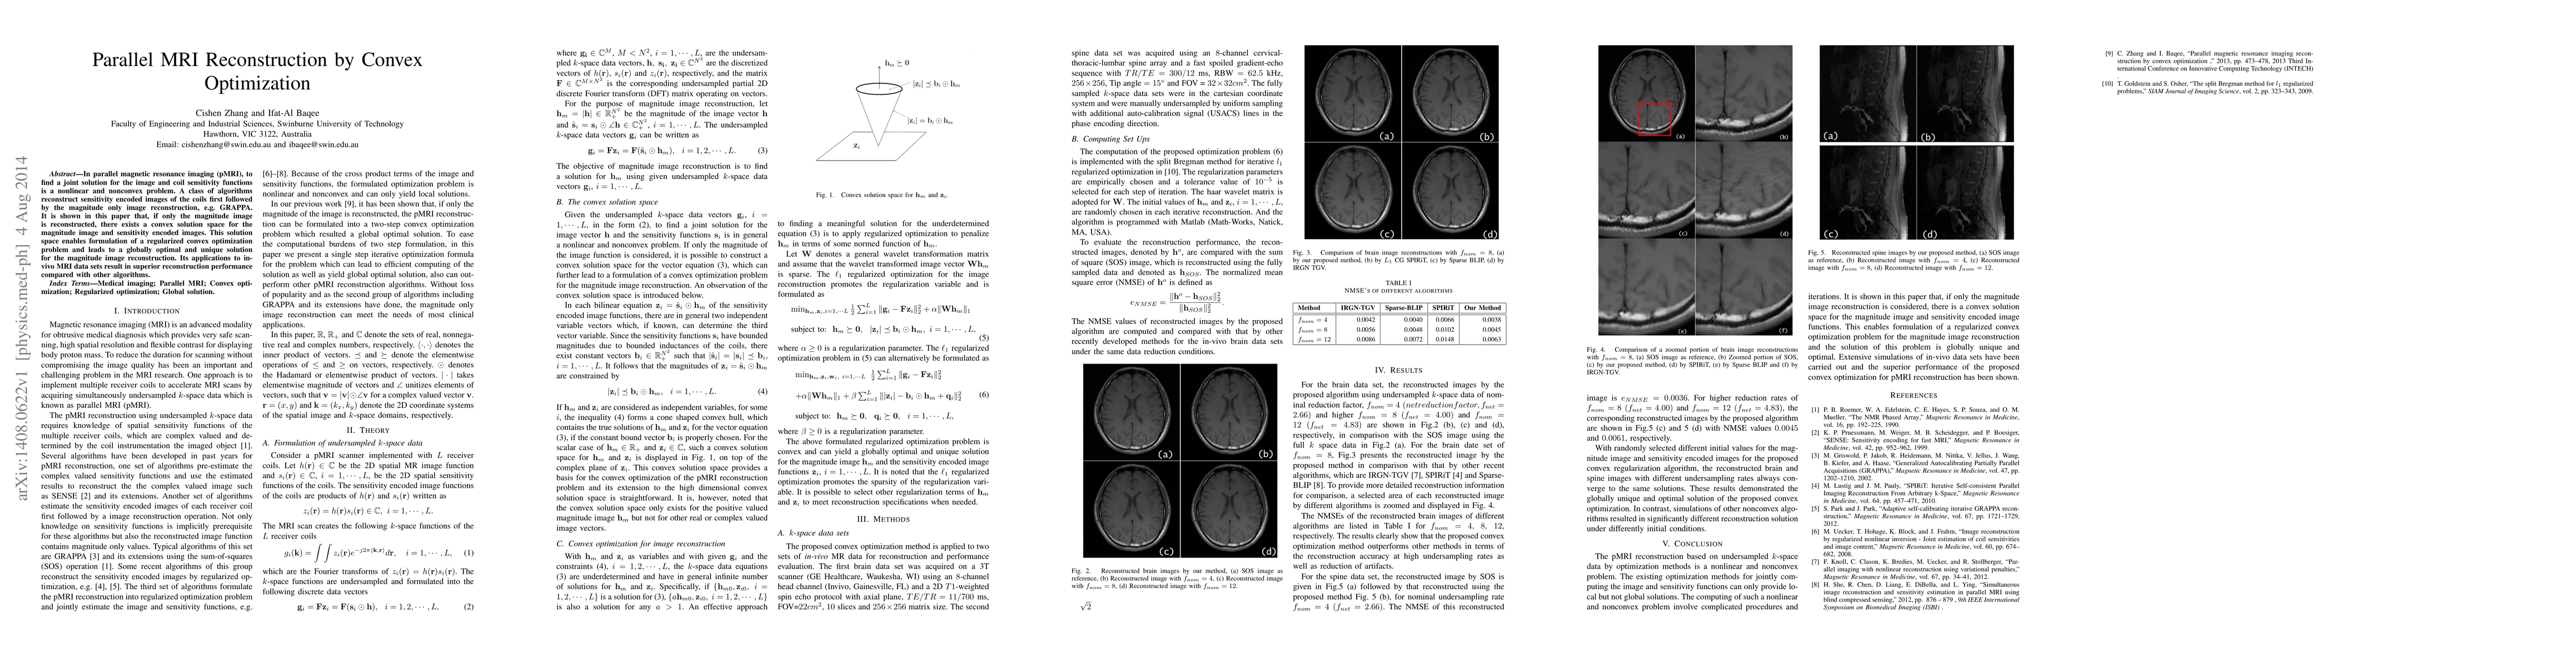

In parallel magnetic resonance imaging (pMRI), to find a joint solution for the image and coil sensitivity functions is a nonlinear and nonconvex problem. A class of algorithms reconstruct sensitivity encoded images of the coils first followed by the magnitude only image reconstruction, e.g. GRAPPA. It is shown in this paper that, if only the magnitude image is reconstructed, there exists a convex solution space for the magnitude image and sensitivity encoded images. This solution space enables formulation of a regularized convex optimization problem and leads to a globally optimal and unique solution for the magnitude image reconstruction. Its applications to in-vivo MRI data sets result in superior reconstruction performance compared with other algorithms.